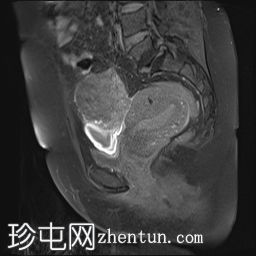

冠状位

T2加权像

可见子宫外腹腔内妊娠囊,内含胎儿组织。

该妊娠囊向后推移子宫,并与剖宫产瘢痕凹陷处紧密相连。

该妊娠囊与相关肠袢无法分离。可见其与性腺血管密不可分,且性腺血管明显突出。

胎盘位于妊娠囊后方,紧贴子宫前壁。

沿妊娠囊下缘可见一处异质性局灶性积液,最大轴向尺寸约为 8.4 × 5.5 cm,T1 加权像呈异质性高信号,T2 加权像呈异质性中等信号,T1 脂肪抑制序列未见信号下降,提示为血液成分。该积液压迫膀胱。

可见周围脂肪间隙呈条索状改变。

左侧卵巢无法辨认。

右侧卵巢未见实性或囊性肿块。

子宫体积增大,后倾,子宫内膜厚度约 1 cm,子宫下段前壁可见局灶性变薄(既往子宫瘢痕)。子宫连接区完整,未见肌层肿块。可见子宫内膜腔边缘有血性分泌物。